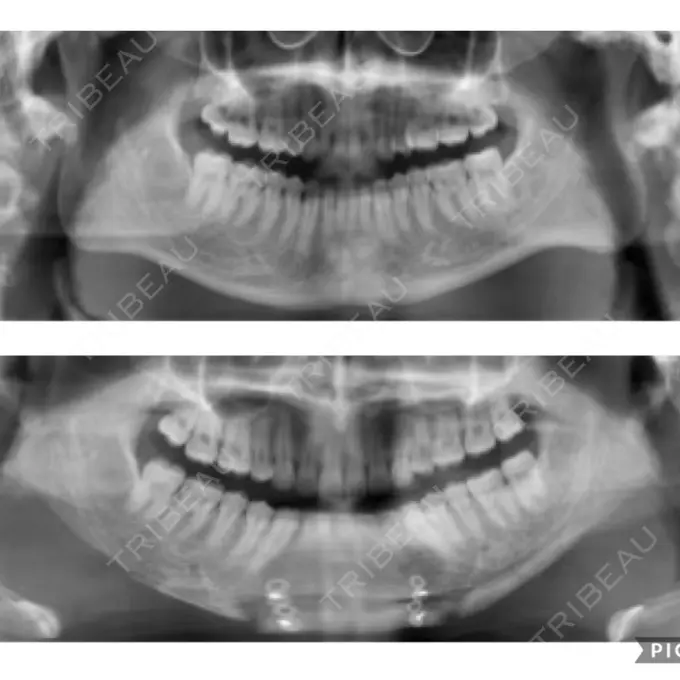

元々、左右差が酷かったので右側をオトガイ神経ギリギリまで切っていただき左はエラ部を中心に切りCTでも左右差が解消されていました。

元々エラ張りに悩んでおり、カウンセリングの際に適応だったこととオトガイも前方移動した方がたるみを防止でき、横顔が綺麗に見えると進められましたので選びました。